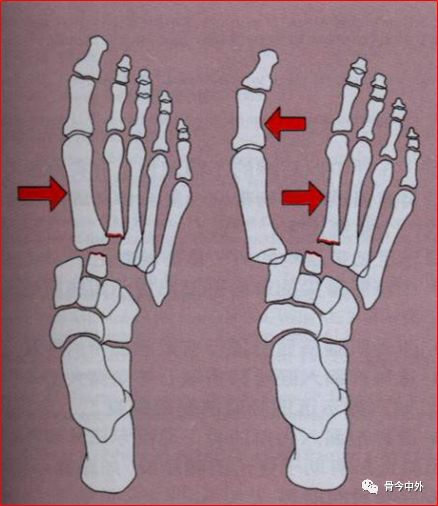

1.Quenu和Kuss分类

• 孤立型:至少一块跖骨而非全部跖骨单向脱位。

• 同侧型:所有跖骨一致向内或更经常是一致向外半脱位或脱位。

• 分离型:跖骨向不同方向或在一个以上平面分离。

既不能评定严重性,也不能确定合理的治疗或评估预后。

2.Myserson改良分类A型:包括全部5块跖骨的移位,伴有或不伴有第2跖骨基底骨折。常见移位是外侧或背外侧移位,跖骨作为一个整体移位。这类损伤常称为同侧型。

B型:一个或多个关节仍然保持完整。B1——内侧移位,有时累计楔间或舟楔关节。B2——外侧移位,可累及第一跖楔关节。

B1——内侧移位;B2——外侧移位

C型:属于裂开性损伤,根据裂开程度分为C1部分裂开、C2全部裂开。这类损伤通常是高能量损伤,应特别注意筋膜间室综合征。

C1部分裂开;C2全部裂开